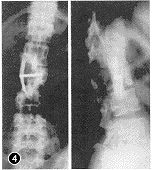

本组23例术后随访最短24个月,最长5年4个月,平均3年8个月。术前脊柱后凸畸形,后凸角18°~45°,平均27.5°,术后为0°~16°,平均6°。17例新鲜骨折病人术后基本矫正(图2~5,插Ⅱ),6例陈旧骨折术后仍有轻度畸形。术后每月摄片1次,骨愈后时间为5~8个月,平均为6个月。术后2例病人出现气胸,均经胸腔闭式引流1周后痊愈。23例病人术前均有不同程度的截瘫,除1例D级为伤后4年,因后凸角较大,故术中做前路植骨,以重建其脊柱中柱、前柱,矫正其后凸成角为目的外,22例均有Frankel一级以上的改善。13例术前有括约肌功能障碍者术后随诊时大部或完全恢复。

图2 X线示L1爆裂骨折 图3 CT扫描示L1前、中、后柱损伤,椎管2/3梗阻 图4 术后随诊X线像示椎体前缘恢复正常高度,椎间隙有骨小梁通过 图5 术后CT扫描示椎管内骨块彻底清除,植骨块与档板位置适中